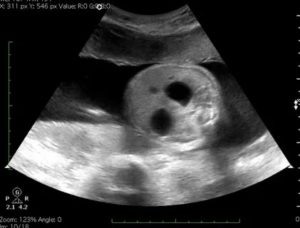

Когда делается первое УЗ-исследование при беременности, нужно измерить «воротниковое пространство». Нормальный размер – максимум 3 мм. При 3 мм и более шея плода начинает отекать, что свидетельствует о хромосомном нарушении и наличии риска появления симптома Дауна.

«Воротниковое пространство» важно измерять при вынашивании близнецов. Чем раньше вы ее обнаружите, тем большей точности будет результат обследования на наличие синдрома Дауна, поскольку именно при многодетной беременности возможны погрешности при обнаружении данного симптома.